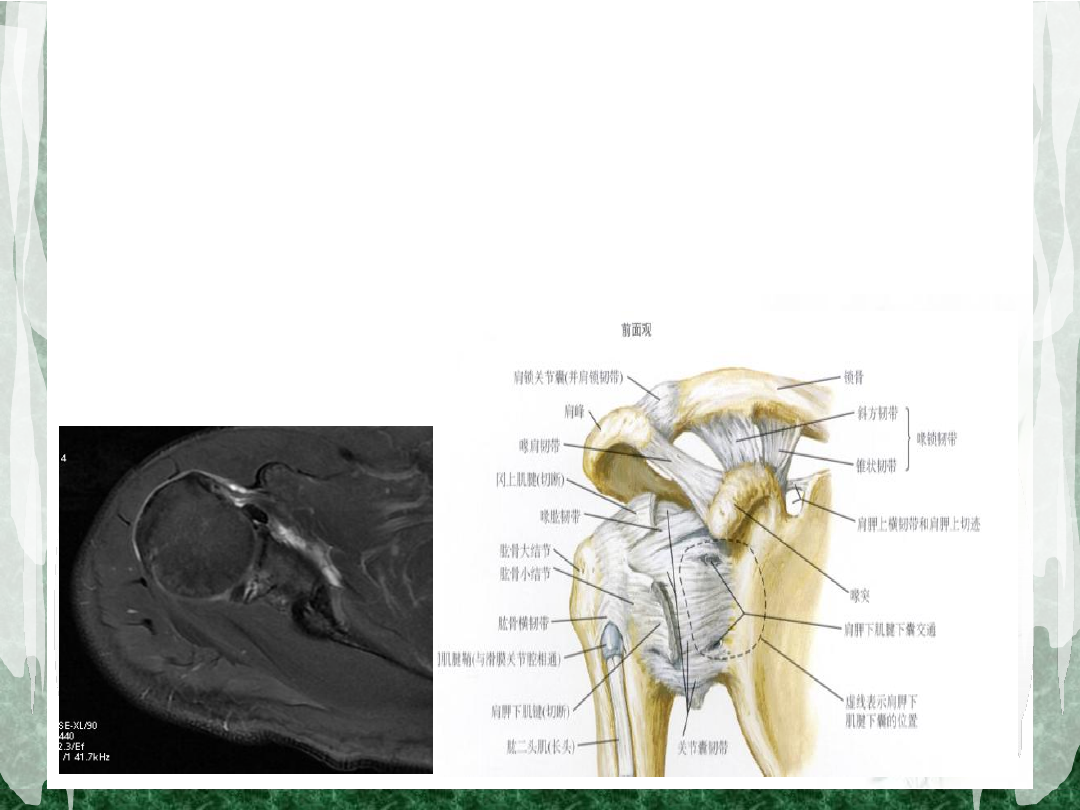

肩袖解剖(一)

组成:冈上肌、冈下肌、小圆肌及肩胛下肌

肩袖解剖(三)

肱二头肌长头腱腱鞘:顶层由冈上肌腱及喙肱韧

带组成,底层由肩胛下肌腱组成。

这种解剖关系提示:肩胛下肌腱撕裂常并发二头

腱长头损伤或脱位